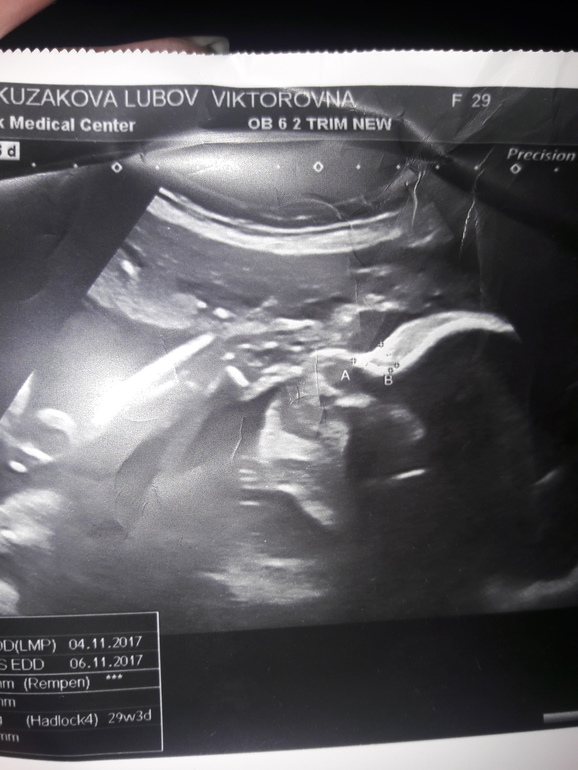

Результаты: УЗИ, КТГ, доплера, скринингаНу вот и мы дождались третье узи😊 Была увененна,что у нас все хорошо,но в заключении написали ВЗРП😣 Как же они меня замучали с этим диагнозом с первым ребенком и вот опять. А все из за того,что окружность живота у доченьки меньше на полторы недели. В общем все остальное у нас по сроку вес в 31 неделю 1460. Подтвердили нам доченьку😁😁😁 И это прекрасно.Малышка моя теперь более активная,что не может не радовать😊 На узи она как обычно прятала личико ручкой🤣Уже третье узи не могу ее разглядеть. А так интересно увидеть ее губки. На кого же она все таки похожа🤔 Папочка наш ходил с нами,умничка, не пропускает такие мероприятия. Фоточку выпросила еле еле. Но на ней особо ничего не видно,опять ручка возле лица😋